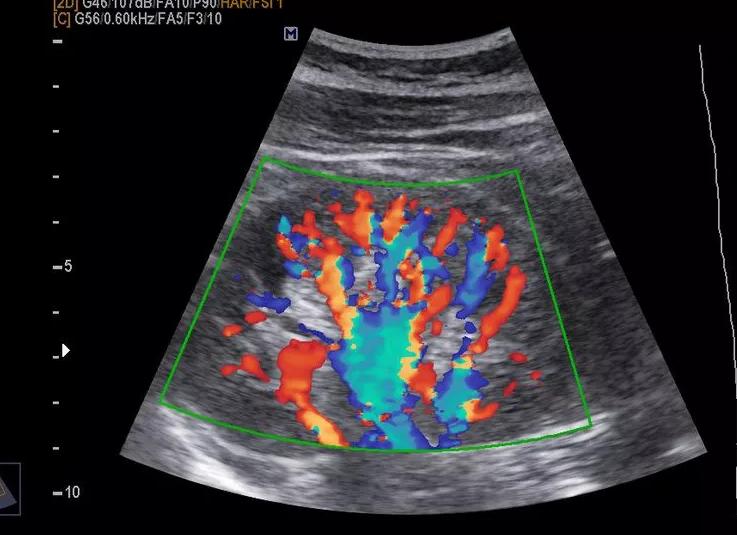

Цветовое допплеровское картирование (ЦДК) представляет собой ультразвуковое исследование с дополнительной оценкой кровотока с помощью допплеровского эффекта, выражающееся в цветном изображении кровотока исследуемого участка, наложенном на черно-белую картину, полученную при УЗИ.

Режим ЦДК позволяет оценить дополнительные параметры, а именно:

• направление движения крови, скорость ее перемещения и другие характерные особенности;

• свободу кровеносного русла;

• сопротивление кровотока;

• размеры сосудистой стенки и диаметр просвета венозной и артериальной сети в различных участках организма.

Мало того, цветовое картирование позволяет обозначить потоки крови с разной скоростью движения различными цветами, то есть создает цветовую картину сосудистой системы органа. Можно в подробностях увидеть структуру и работу каждого отдельного сосуда, выявить патологии самих сосудов, а также обнаружить опухоли — в них отсутствует обычная система кровоснабжения.

Она особенно необходима в том случае, если предполагаемая патология имеет прямую или косвенную связь с работой или состоянием сосудов. Если при ультразвуковом исследовании на экране монитора появляется только черно-белое изображение, то цветовое картирование показывает цветные элементы в области исследования. Нужно понимать, что красный и синий цвет означает не вены и артерии, а демонстрирует направление движения крови — от датчика или к нему. Опытный специалист в этой области отлично знает все тонкости такого способа диагностирования, а специальные таблицы на экране прибора помогают в проведении точной оценки проблем.

Добавление ЦДК в УЗИ: что это? Данное исследование представляет собой добавление к обычному черно-белому УЗИ допплеровской оценки кровотока. Допплеровский эффект дает возможность организовать посылку и обратное получение ультразвука посредством определённого датчика. Кровоток в режиме ЦДК в зависимости от направления и скорости движения имеет оттенок одного из цветов. Если целью направления кровотока является датчик, то кодироваться будут красные тона, если имеет место обратное направление кровотока – синие.

Система васкуляризации опухоли, как правило, представлена множеством мелких, очень тонких, аномальных по форме и расположению сосудов, хаотично разбросанных в пределах опухолевых тканей. Кровоток в этих сосудах характеризуется крайне низким сосудистым сопротивлением, высокой скоростью и разнообразным направлением. Изображение кровотока при этом отличается выраженной яркостью цветового сигнала, а в «окраске» опухолевых тканей могут преобладать как основные цвета, так и «мозаичная» форма картирования. Эти особенности кровотока обусловлены наличием большого количества артериовенозных анастомозов среди новообразованных сосудов, которые обеспечивают высокую кинетическую энергию кро-вотока и объясняют широкую вариабельность его направления [5].